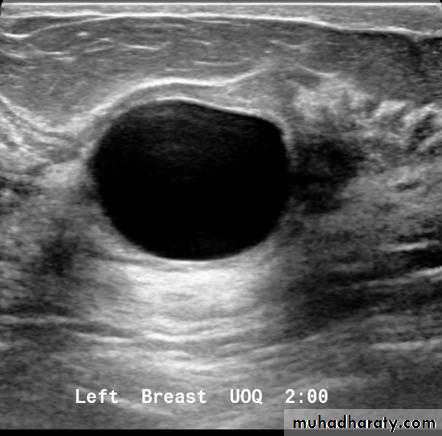

Cysts can be simple fluid-filled sacs (known as simple cysts) or can be partially solid (known as complex cystic and solid masses). Simple cysts are benign (not cancer) and don’t need to be biopsied. If a mass is not a simple cyst, it is of more concern and might need to be biopsied to be sure it isn’t cancer

CYST

mammogram